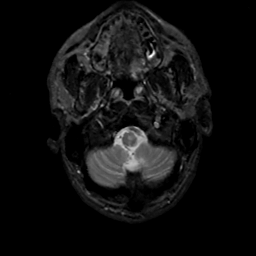

MR Study #12, May 12, 1991 -- Slice #4

[Home][Help][Clinical][Tour 1][Tour 2] Slice 4